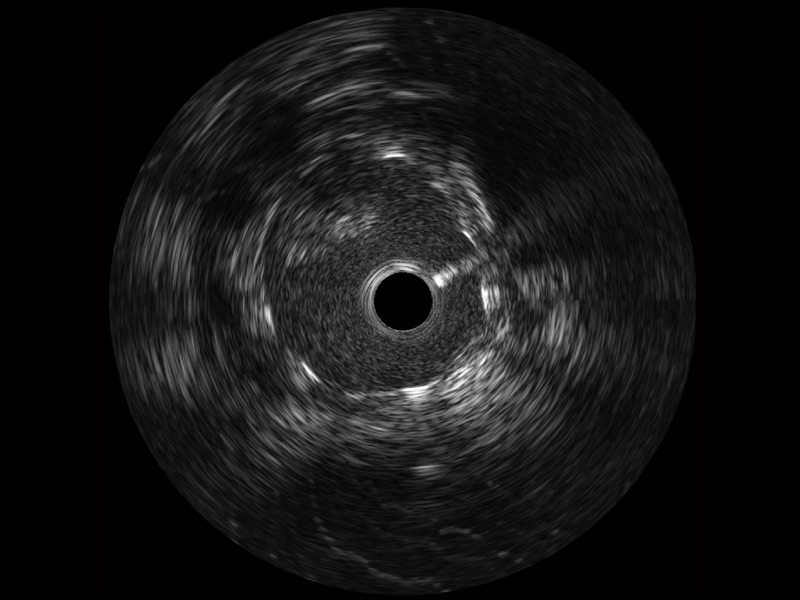

公海贵宾会员检测中心宽频IVUS图像

传统IVUS图像

对比传统IVUS导管成像,公海贵宾会员检测中心宽频IVUS图像的近场支架梁显影更细腻,远场中膜外血管仍清晰可辨,兼顾远中近,兼顾分辨力与穿透深度